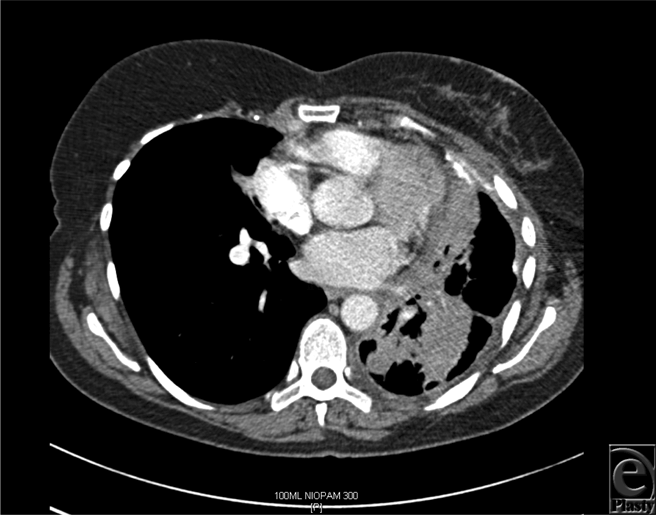

The median time interval between mastectomy and DBR was 28 months (range = 20-120 months), whereas the median time interval between DBR and local recurrence was 7 months (range = 4-10 months). Figures 1a to 1c show the reconstruction, recurrence, and postradiotherapy status of patient C. The patient with the longest time interval between mastectomy and DBR (120 months) developed chest wall recurrence only 4 months after her reconstruction (patient A). She also developed intrapleural metastases and intrapulmonary nodes (Fig 2). She subsequently developed bone and peritoneal metastases and is currently receiving palliative treatment but remains alive 44 months following her recurrence. The other 2 patients have died as a consequence of metastatic disease, 36 and 72 months following their local recurrence.

| Figure 2. Computed tomographic scan of patient A demonstrating intrapleural metastases, intrapulmonary nodes, and thickening of the left pleural surface. |